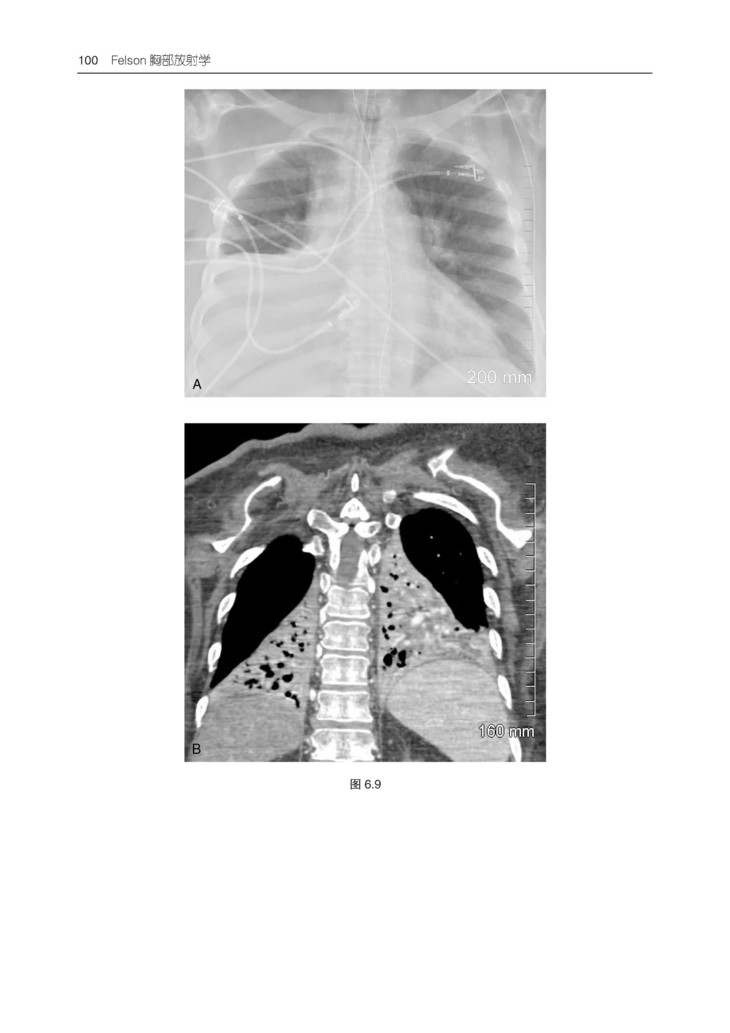

本书易于阅读、引人入胜,长期以来一直是广大放射科医学生和医生的首选学习资源。本书提供了有关胸部影像学方面的所有内容,包括病理学和解剖学难题,以通俗易懂的方式对基础理论、影像判读方法和专业术语进行了阐释。紧跟学科前沿,包括胸膜肺实质纤维弹性组织增生症、合并肺纤维化与肺气肿、与年龄相关的肺部变化、间质性肺病、肺癌筛查和肿瘤分类,以及降低辐射剂量和安全考虑等热点话题。

3.包含550 余幅高质量影像图片,并根据需要配有相关的PET、CT 和 MRI 图像。